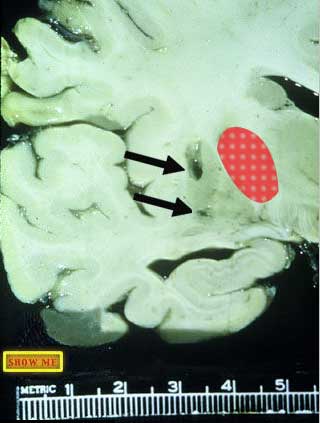

Can you see the two small infarcts in the putamen? (The red area is the internal capsule)